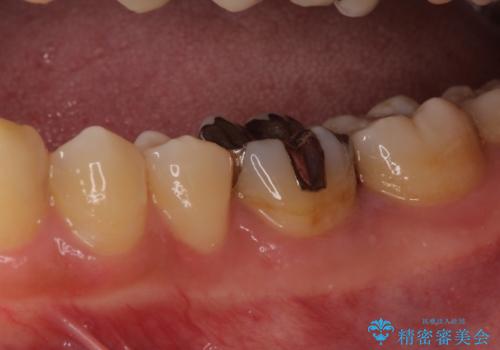

- 左下奥歯の銀歯のつめものがとれたことを主訴にご来院された患者様です。

1番奥の歯のセラミック治療をご希望されましたが、レントゲンなどの診査の結果、大きな虫歯などもありませんでした。

それよりも奥から2番目の歯のほうが、適合不良の銀のつめものが入っており、大きな虫歯が疑われました。

虫歯の大きさや形を加味して、1番奥を保険治療、奥から2番目をセラミック治療で行うことになりました。